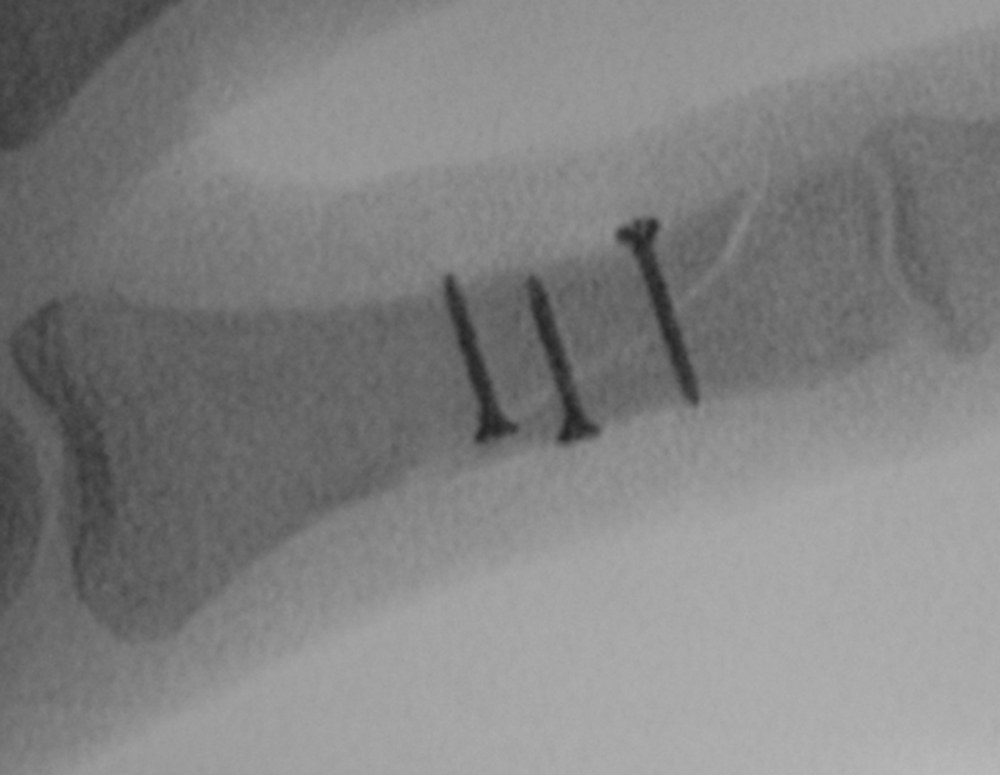

If the fracture can be held in position with one, or two bone-holding forceps, you can fix it with screws (which must be placed perpendicular to the fracture, not perpendicular to the bone) ( Fig. 56.4 ).

Intramedullary headless screw fixation of metacarpal fractures (and phalangeal fractures) is also possible and this method allows for very early mobilization, no periosteal stripping with dissection (and hence no potential subsequent tendon adhesion) or sticky-out metal work (K-wires), though it does violate the articular cartilage.